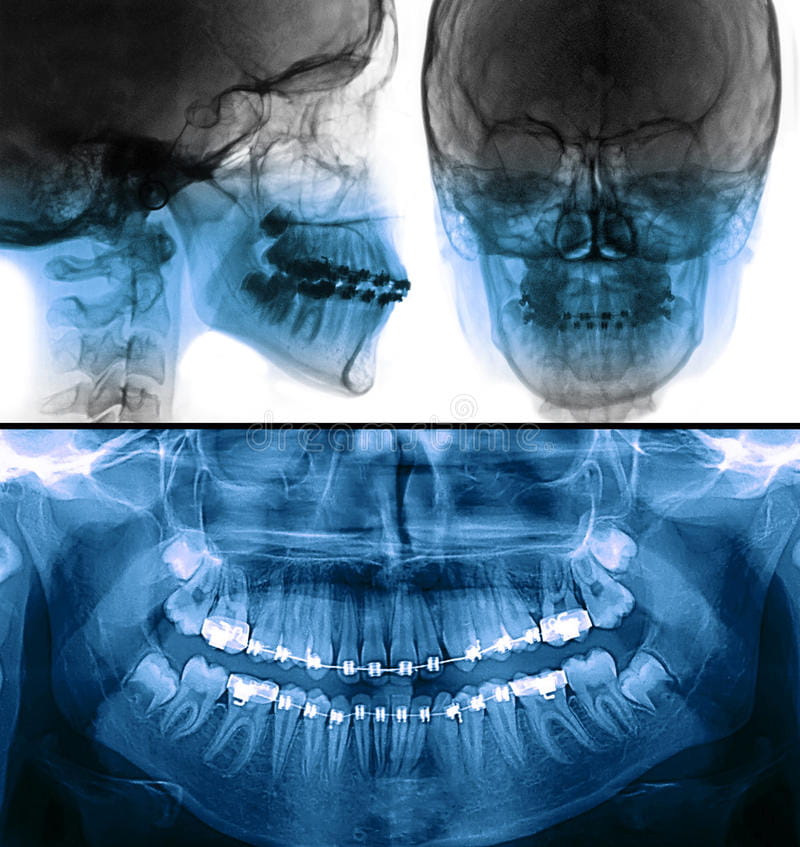

Extra Oral:

- Frente

- Perfil

Intra Oral

- Frontal

- Lateral (derecha e izquierda)

- Oclusal (superior e inferior)